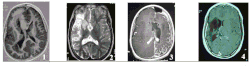

1) Malformation du cortex cérébral anténatal (figure A.1) : il s’agit d’une anomalie majeure du développement d’un hémisphère cérébral par trouble de la migration et de la différenciation neuronale conduisant à une organisation pathologique du cortex et des crises d’épilepsie sévères et rebelles dès les premiers jours ou premières semaines de vie. Dans certains cas, l’hémisphère est anormalement gros et on parle d’hémimégalencéphalie (un des deux hémisphère cérébral est plus gros que l'autre et malformé, généralement facilement identifiable à l'IRM).

2) Encéphalite de Rasmussen (figure A.2) : c’est une encéphalopathie épileptique et inflammatoire sévère, d’étiologie inconnue ; elle s’exprime par une épilepsie rebelle associée à une inflammation et une nécrose focale et extensive du cortex d’un hémisphère cérébral puis évoluant vers son atrophie responsable d’un déficit progressif neurologique, moteur et cognitif. Elle apparaît avant l’âge de 10 ans dans 85% des cas, chez des enfants ayant eu un développement normal auparavant.

3) Le Syndrome de Sturge-Weber (figure A.3), est une neurofibromatose, associant de façon variable une anomalie cutanée - angiome facial -, ophtalmologique - glaucome - et cérébrale - angiome pial hémisphérique. Les crises d’épilepsie surviennent le plus souvent dès la première année de vie sous forme d’état de mal hémicorporel sévère suivi d’un déficit permanent. Avant ces crises, les enfants peuvent avoir un développement proche de la normale bien que la pathologie soit anténatale (avant la naissance).

4) Une séquelle d’accident vasculaire (figure A.4) le plus souvent périnatal précoce (porencéphalie, thrombose de l’artère sylvienne, hémorragie cérébrale, méningite néo-natale), ou post-natal (accident ischémique ou hémorragique, syndrome Hémiconvulsions-Hémiplégie-Épilepsie, …). Les enfants présentent un tableau d’hémiplégie cérébrale infantile avec développement lent ou subnormal ; les crises d’épilepsie apparaissent secondairement et viennent aggraver les troubles neurologiques préexistants.

Les images d’Imagerie par Résonance Magnétique (IRM) de la figure A illustrent ces quatre grands groupes étiologiques.

Ainsi, ces pathologies cérébrales conduisant à proposer une déconnexion hémisphérique constituent quatre groupes étiologiques que l’on peut différencier selon leur âge d’apparition : pathologie anténatale (figure A.1), post-natale tardive (figure A.2), péri ou post-natale précoce (figure A.3 et figure A.4).